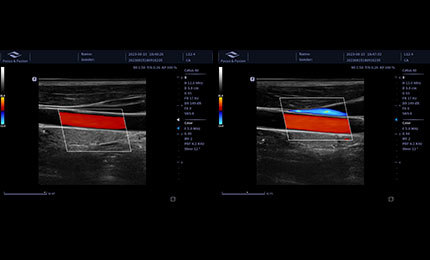

Auto Volume Flow

Urządzenie umożliwia pomiar obszaru naczynia krwionośnego, automatyczne określenie prędkości przepływu krwi w oparciu o analizę widmową oraz prezentację wyników objętości przepływu.